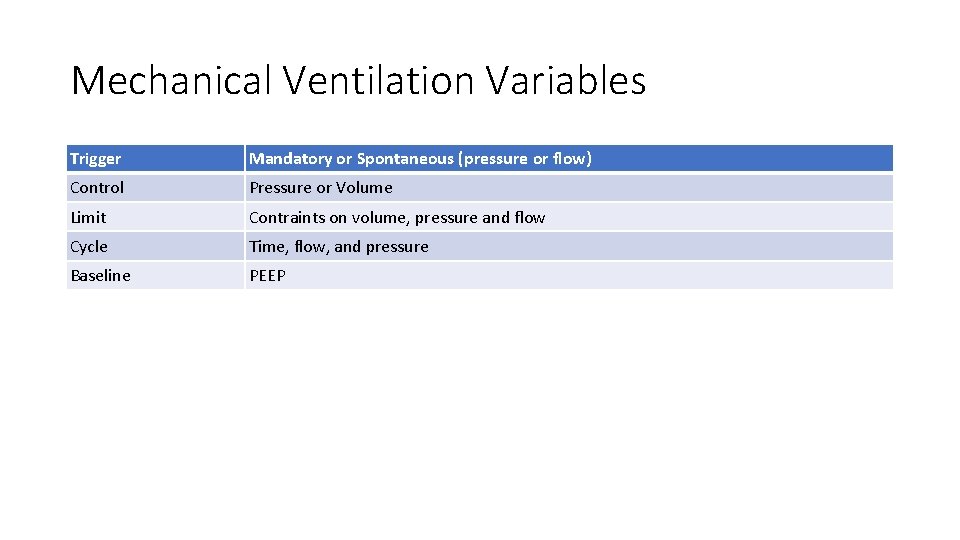

Mechanical Ventilation Variables Trigger Mandatory or Spontaneous (pressure or flow) Control Pressure or Volume Limit Contraints on volume, pressure and flow Cycle Time, flow, and pressure Baseline PEEP